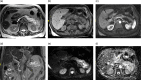

Intraductal papillary mucinous neoplasms (IPMN) of the pancreas have the potential for malignant progression into adenocarcinoma. Colloid or mucinous non-cystic carcinoma of the pancreas is an uncommon variant neoplasm that can arise within an intestinal type IPMN and have a relatively improved prognosis but may mimic the more lethal tubular or ductal adenocarcinoma. Colloid carcinoma is an infiltrating ductal epithelial neoplasm containing primarily extracellular stromal mucin pools and scant amount of centrally floating neoplastic cells. While several reports have evaluated the unique pathologic and immunohistochemical profile of colloid carcinomas, there has been limited radiologic-pathologic correlation in the literature. We report a case of an 83-year-old female who presented for evaluation of slowly progressive abdominal pain and was found to have colloid carcinoma arising from an IPMN. This is one of the first reports to correlate the multimodality radiology including cinematic rendering (CR) and histopathology features associated with this tumor. An enhanced understanding of the correlation between imaging appearance and specific histopathologic findings may aid in the early recognition and treatment of this rare neoplasm. Emphasis is placed on CR as this may help guide surgical management.